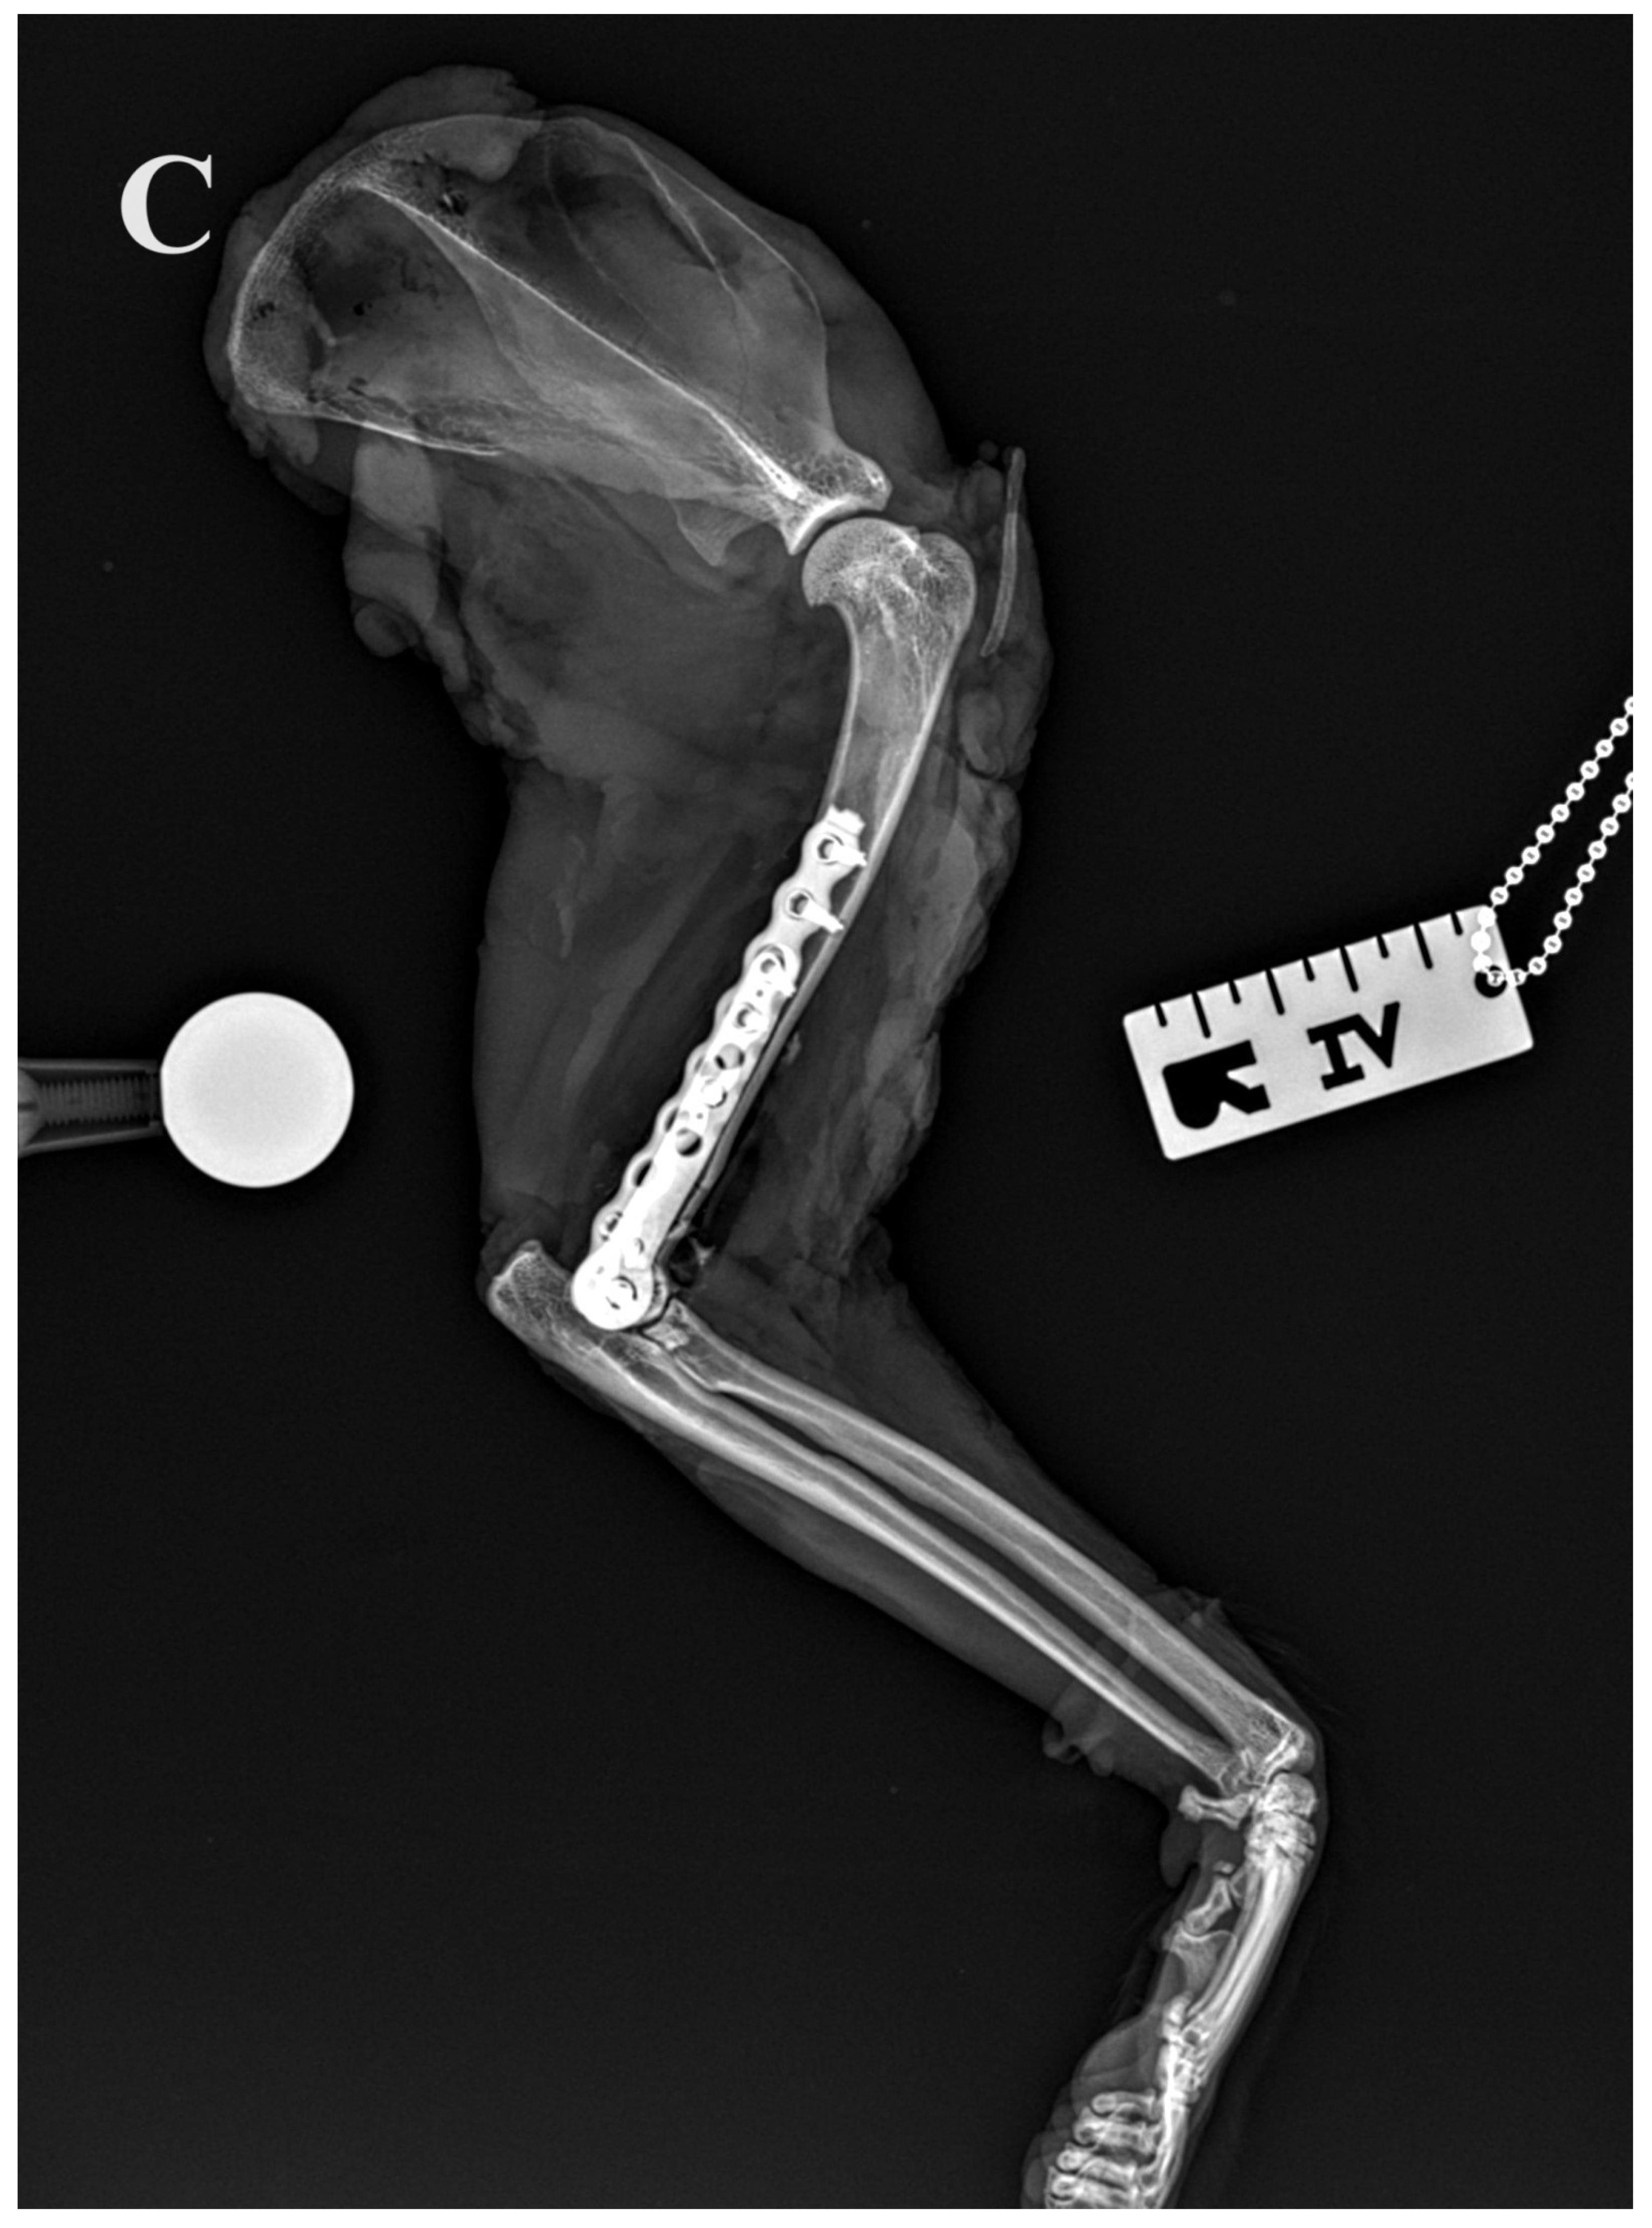

Figure 5.

(A,B) Initial lateral and cranio–caudal radiographs of the right forelimb of a female domestic cat show a displaced Y-T fracture. (C,D) Postoperative lateral and cranio–caudal radiographs show a small articular surface defect (<1 mm) of humeral condyle and adequate alignment, adjacency and apparatus (2.0/2.4/2.7 3D printed plate, 2.4/2.7 straight interlocking bone plate and screws).